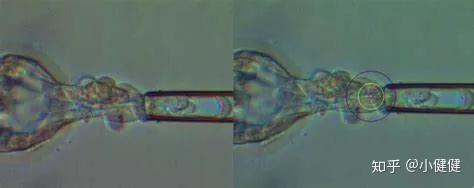

3.囊胚的滋養層細胞活檢:

體外培養的胚胎通常會在第5、6天發育至囊胚,此時胚胎的細胞數目明顯增多,可以達到100個以上。囊胚的滋養層細胞將來會發育成胎盤或胎膜,不參與形成胎兒部分。因此,活檢囊胚的滋養層細胞,不僅能夠最大程度地反映胚胎的遺傳信息,而且也能夠避免對胎兒部分的損傷。囊胚的滋養層活檢可以獲得的細胞數目增多,而且囊胚期胚胎染色體嵌合比例顯著低于卵裂期胚胎,這些都提高了遺傳診斷的準確性;同時囊胚的培養技術、玻璃化凍融技術越來越成熟以及激光儀器的發展也為囊胚活檢的廣泛應用提供了技術保障。